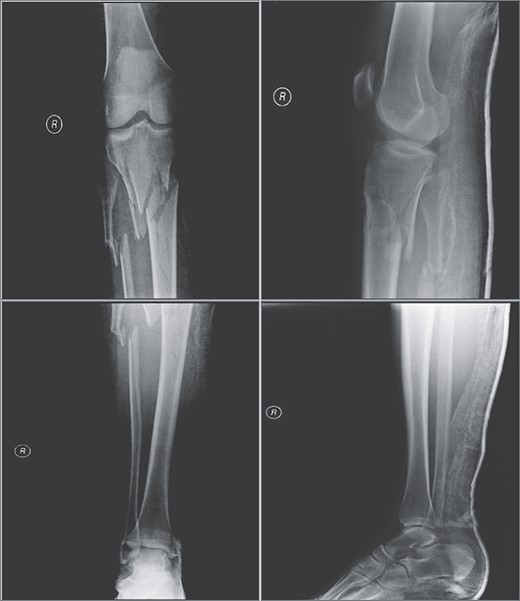

A 39-year-old male pedestrian was injured in a motor vehicle accident and then transferred to our emergency room on the same day of injury. Patient was stable after the accident and medical history was noncontributory. Physical examination of the right leg demonstrated considerable soft-tissue swelling around the knee and proximal tibia deformity and no signs of neurovascular injury. Imaging revealed a Schatzker type VI tibial plateau fracture (Fig. 1). Computer tomography angiography revealed no vascular damage. The leg was immobilized with a splint, adequate analgesia was prescribed and the patient was admitted to ward.

Radiographic views demonstrating a complex proximal tibia fracture of the right leg.